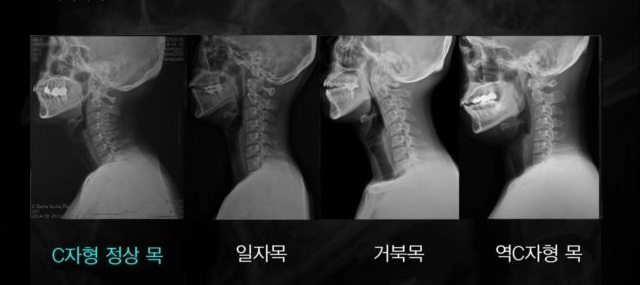

거북목 증후군, 현대인들 대부분 달고 사는 증후군이라고 할 정도로 흔한 거북목 일자목이랑 거북목이랑 비슷비슷한데요. 아파서 병원을 가시는 것도 중요하긴 한데, 거북목 같은 경우에는 미리미리 예방하는 것이 가장 중요합니다. 컴퓨터나 스마트폰 오래 쓰시는 분들 거의 대부분 걸리신다고 보면 되는데, 그 이유는 컴퓨터나 스마트폰 할 때 자세가 이상하면 많이 걸리는 거라고 생각하시면 됩니다.

일자목, 거북목 주의